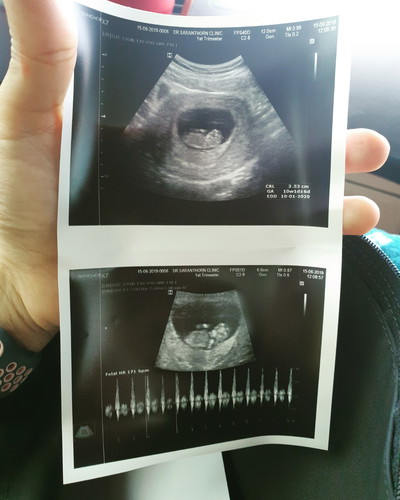

10w+1 เห็นลูกแล้วจ้า

กว่าจะได้เจอตัวอ่อน แม่เห็นปุ๊บ น้ำตาไหลเลย

เพิ่งไปซาวด์มาเมื่อเช้าก็เจอแล้วค่ะ10w+6 ก่อนหน้านั้นซาวด์ตอน6w+1เจอแต่ถุง หมอบอกอาจท้องลม ตอนนี้สบายใจขึ้นเยอะเลยค่ะ

เข้าใจความรู้สึกเลยค่ะ บ้านนี้ก็แอบน้ำตาซึมเหมือนกัน😄

แปลกนะค่ะ ดูกี่ทีก้ไม่เบื่อ บางทีหยิบมาดูซ้ำไปซ้ำมา